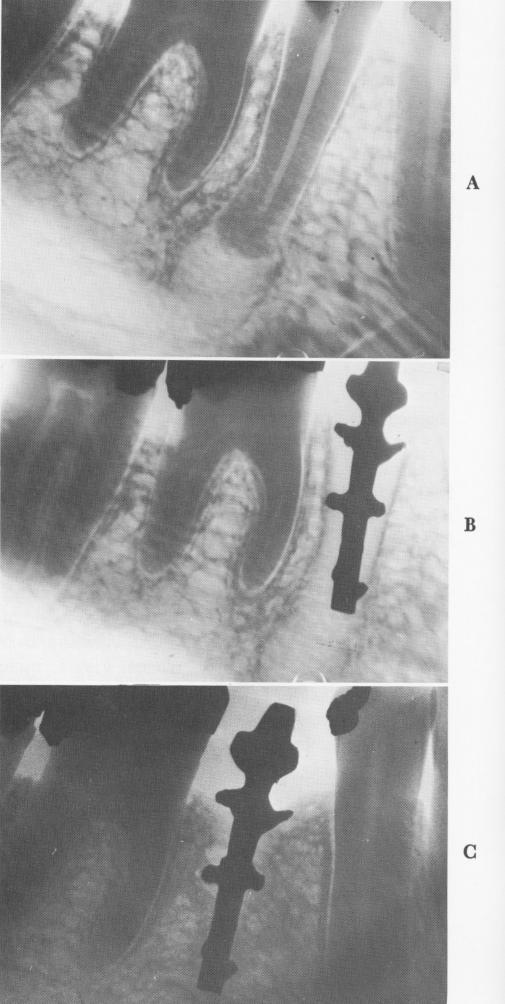

Fig. 5-19. A, A large granuloma is found around the apex of the second bicuspid to be replaced by a Lee implant. B, Some bone regrowth is seen 9 months after the implant's insertion into the open socket. C, Thirteen years later, the implant is still quite secure and functioning well, with bone practically totally surrounding the implant. (Courtesy T. C. Lee.)

One of the more successful post designs is that of the Chinese-American Ted Lee (Fig. 5-18) . The central post is narrow, with small extensions that pro-vide security against exfoliation. The spacing between the extensions and the narrowness of the post allow blood- and bone-building elements to encompass the major part of the implant.

Fig. 5-18. The protruding extensions of this Lee implant give the implant the same diameter as the incisor which it is to replace. (Courtesy T. C. Lee.)